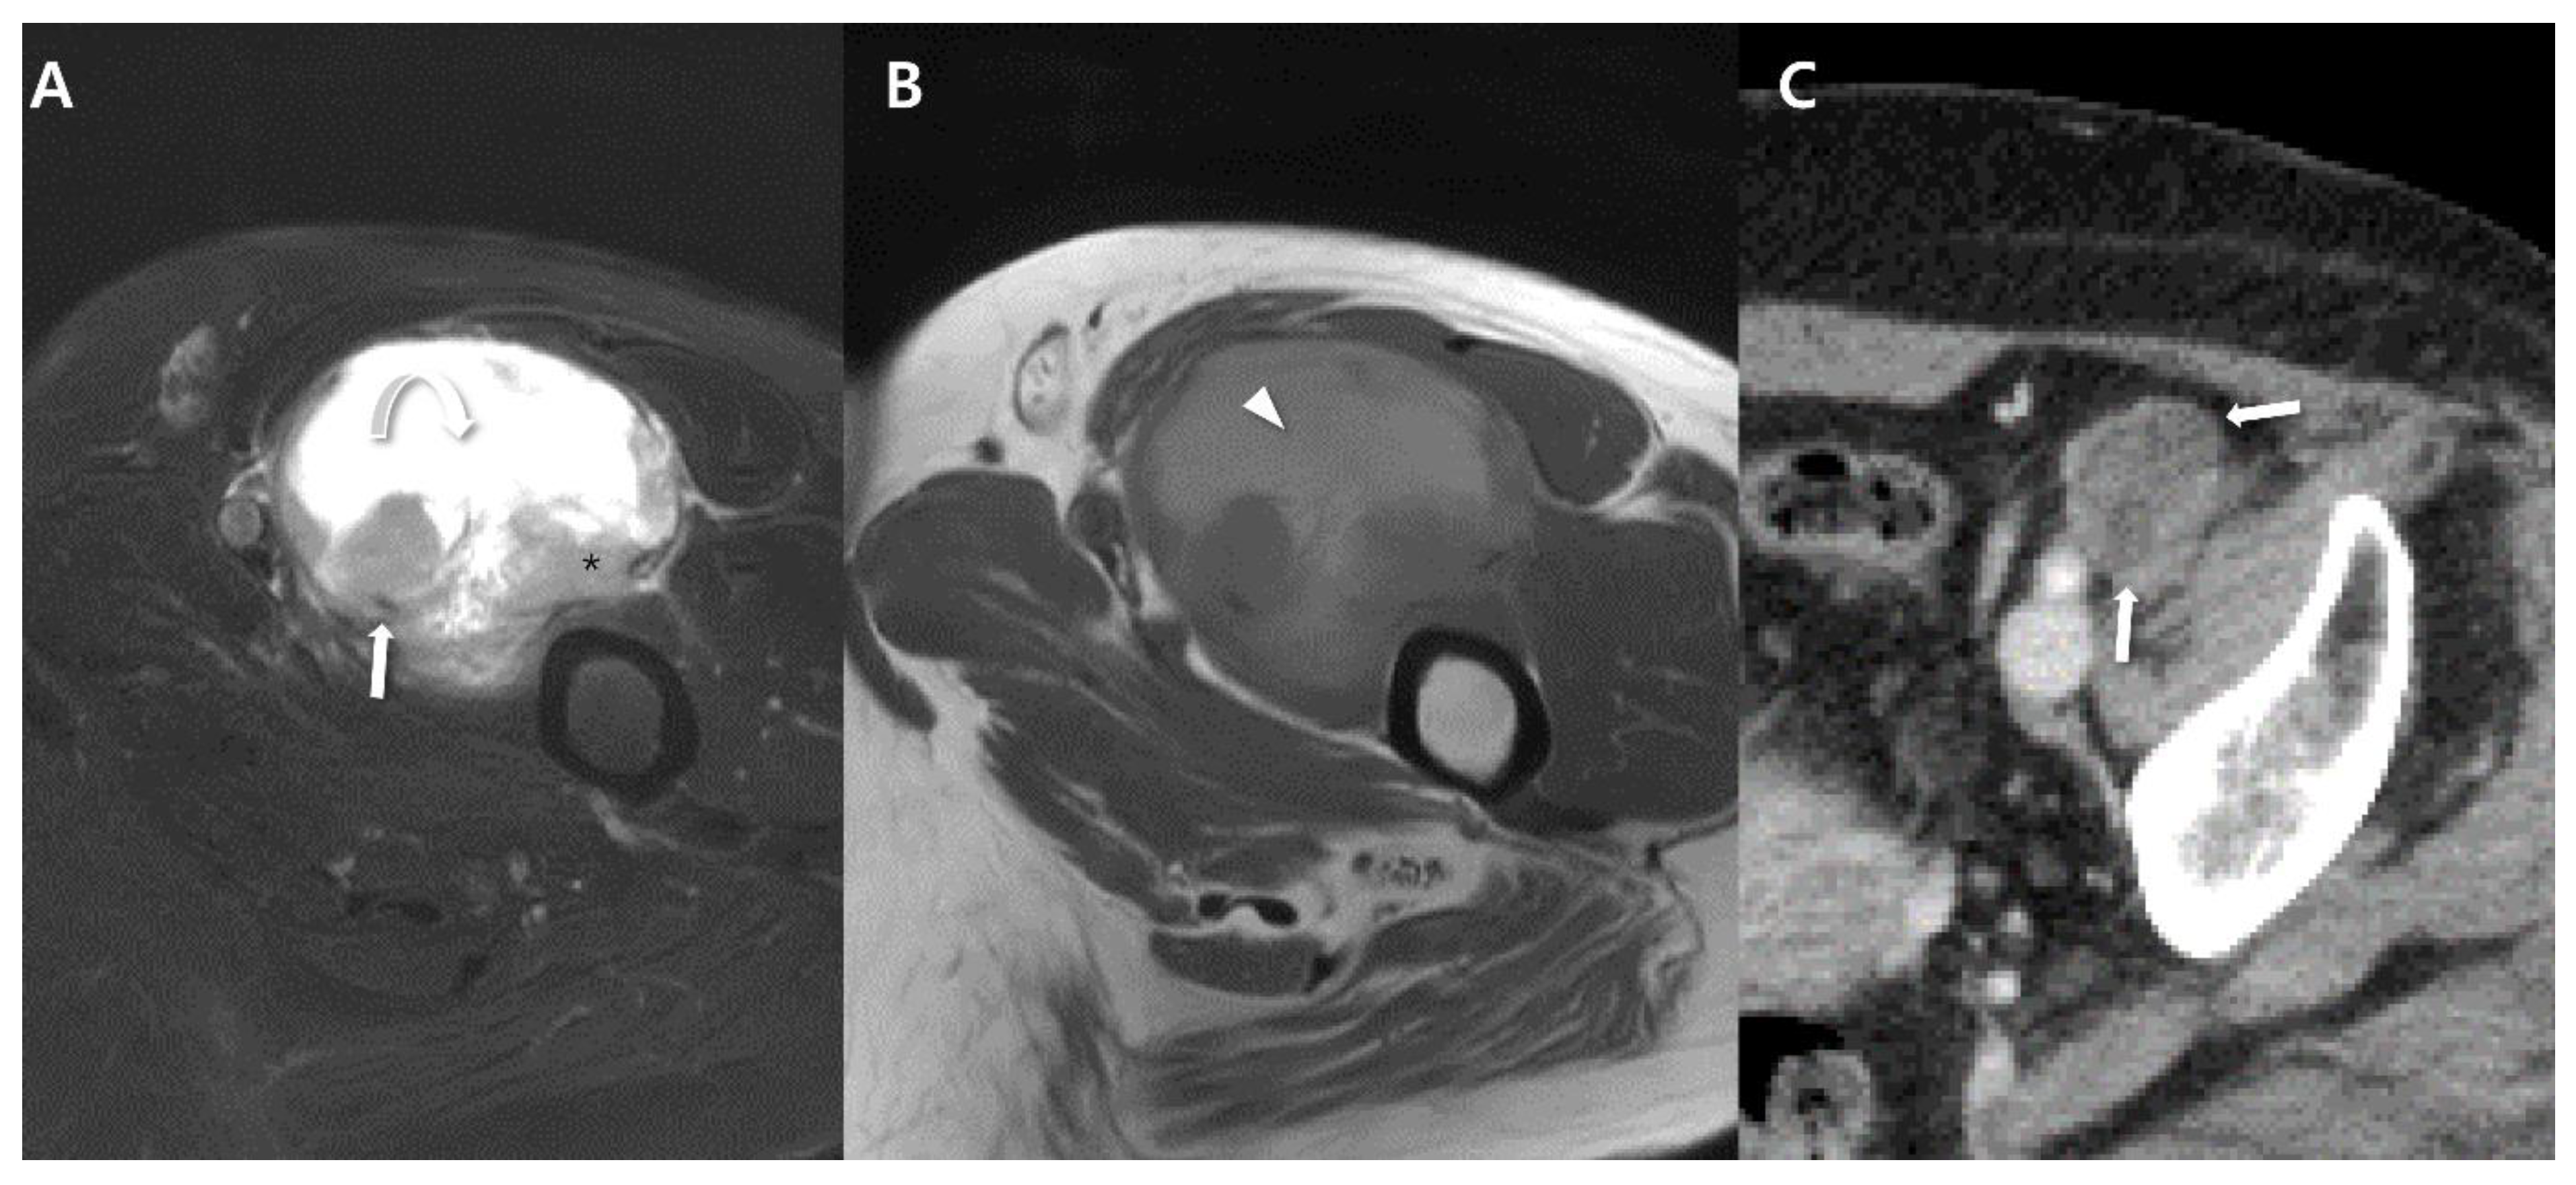

2.4. Magnetic Resonance Imaging (MRI)

2.5. Advanced MRI

3. Uncommon Primary Sites of Synovial Sarcoma in the Extremities

| Imaging features | Intratumoral hemorrhage (fluid-fluid levels) | Poor |

| Triple sign on MRI | ||

| Intercompartment extension | ||

| Peritumoral enhancement | ||